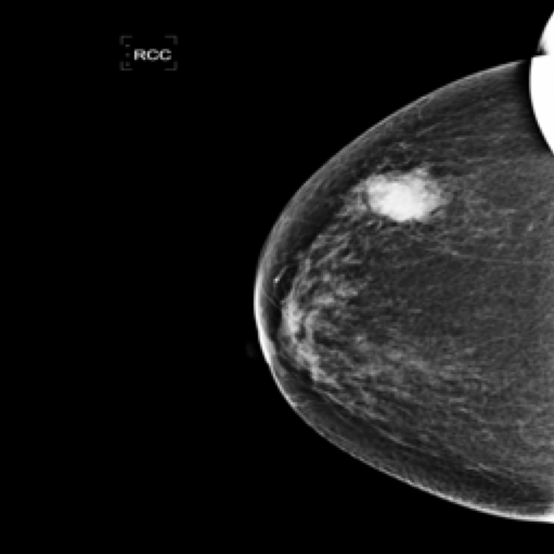

Fig. 1 illustrates the workflow of radiologists in assessing suspected breast lesions. This process begins with the radiologist drawing on both the consensus in radiology and their experience. They observe the lesion from various perspectives, focusing on its manifestations such as shape, contour, and density. The findings are then documented in mammography reports. This workflow encompasses three key elements: 1) Mammography Images providing visual information. However, the disease-related features in these images are often complex and subtle, making accurate interpretation challenging. 2) Manifestations representing the expert knowledge in analyzing breast lesions, which are rich in dense, semi-semantic information. 3) Mammography Reports standing for the linguistic summaries of the radiologist’s observations with containing highly sparse and abstract semantic information. The reports encapsulate the radiologist’s final interpretation and conclusions based on the visual and manifestation data.

Mammography Imaging. In radiological examinations, multiple views are captured to thoroughly represent lesions. For mammography, these typically include four views: left mediolateral oblique (LMLO), left craniocaudal (LCC), right mediolateral oblique (RMLO), and right craniocaudal (RCC). To ensure dataset completeness and versatility for various tasks, we retained all views in their original form, irrespective of the presence breast lumps. However, views without breast lumps are not involved in this study.